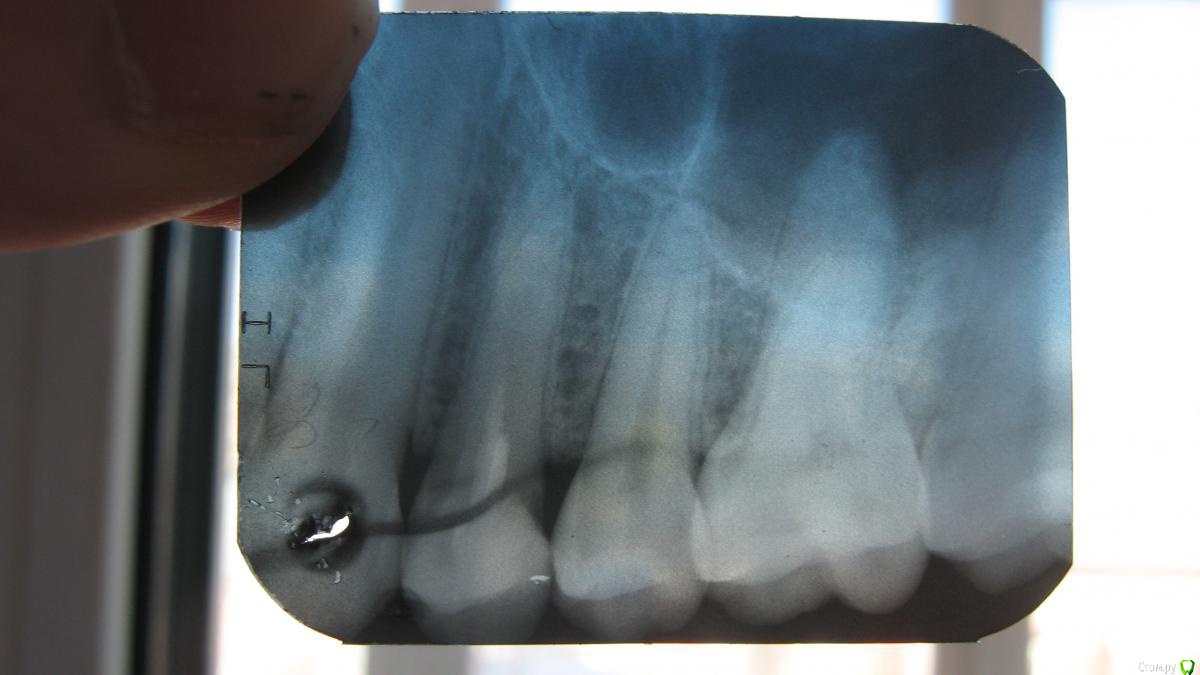

sasha35 Опубликовано 21 марта, 2015 Поделиться Опубликовано 21 марта, 2015 Здравствуйте. Осенью 2014 года лечил 4 зуб вверху. На 2 день после установки пломбы была боль, которая прошла через несколько дней. Со временем обнаружил, что больно нажимать на верхушку корня. Сам по себе не болит.Сделал снимок зуба, сходил к стоматологу. Он сказал, что плохо запломбирован канал. Я отказался вскрывать зуб. Сейчас появилась необходимость сделать СКТ ППН (для испр. носовой перегородки). Обнаружена киста в/ч пазухи, с той стороны где этот зуб(7*8мм) Сделал панорамный снимок челюсти, пошел к челюстно-лицевому хирургу. Он на снимке ничего не нашел. Тоже сказал, что зуб плохо запломбирован и возможно идет воспаление. Кисты на снимке нет. Может такое быть, на СКТ киста есть, а на рентгене нет? Выходит либо кистане связана с зубом, либо на СКТ воспаление показало как кисту? К кому мне обращаться? Ссылка на комментарий

sasha35 Опубликовано 22 марта, 2015 Автор Поделиться Опубликовано 22 марта, 2015 СКТ и рентген зуба. Панорамного снимка нет. Ссылка на комментарий